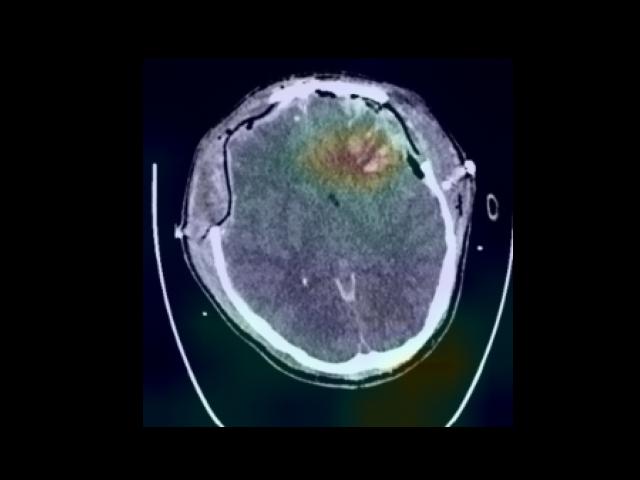

Sample Gallery